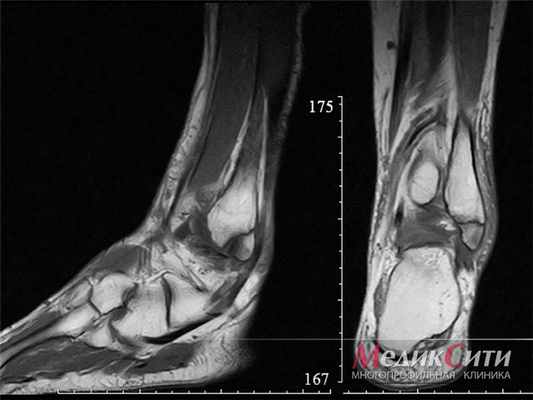

МРТ голеностопа: перелом лодыжки

МРТ колена: норма